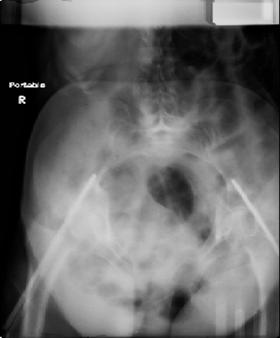

attached are images of a 70 year old female after peds versus car. her own car ran her over.

injuries are limited to the pelvis. left rami open and visible in a 10cm vertical laceration just lateral to left labia majora. wound is grossly clean. no vaginal and no urinary issues. CT scan shows widening of both SI joints anteriorly but I think this is vertically stable pattern.

pt treated that night with I/D and supra-acetabular frame to close the ring. consideration was given for SI screws bilateraly, but given time of night and other factors decision made not to proceed.

so the question is what next operatively if anything? concerns are infection, nonunion anteriorly and possible incompetence of the pelvic floor which may lead to prolapse issues. right rami are comminuted and plating may entail ilioinguinal approach to extend plate laterally to right iliac wing. retrograde screw up right rami is an option but I am not convinced it will add much. adding SI screws very doable, but major concern is restoring anterior ring. so far wound is clean and closed over a drain, and I have no plans to open it back up and wash again.

maintaining pelvic alignment in ex-fix in 70 yo female for any length of time may be challenging.

any thoughts? would anyone plate the pubic symphysis to close the gap and leave the more lateral rami fractures alone? the most recent pelvic case on this website involved pts with suprapubic catheters and antibiotic options including resorbable beads. I wonder how many people would plate and place antibiotic beads. thanks.

attached are several CT cuts. please let me know if you need more. the CT is pre-pelvic ex-fix placement.

Thank you.